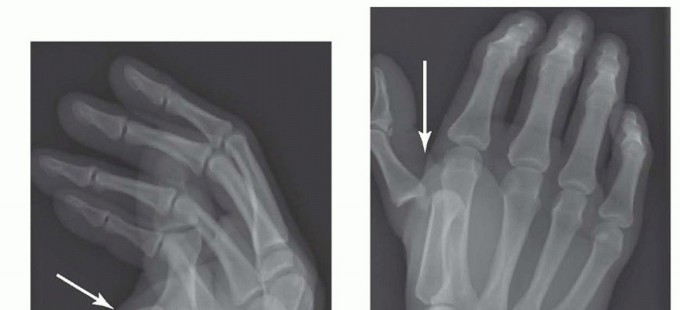

FIG 2 • X-rays showing MP joint dislocation on AP (A) and lateral (B) films. (continued)